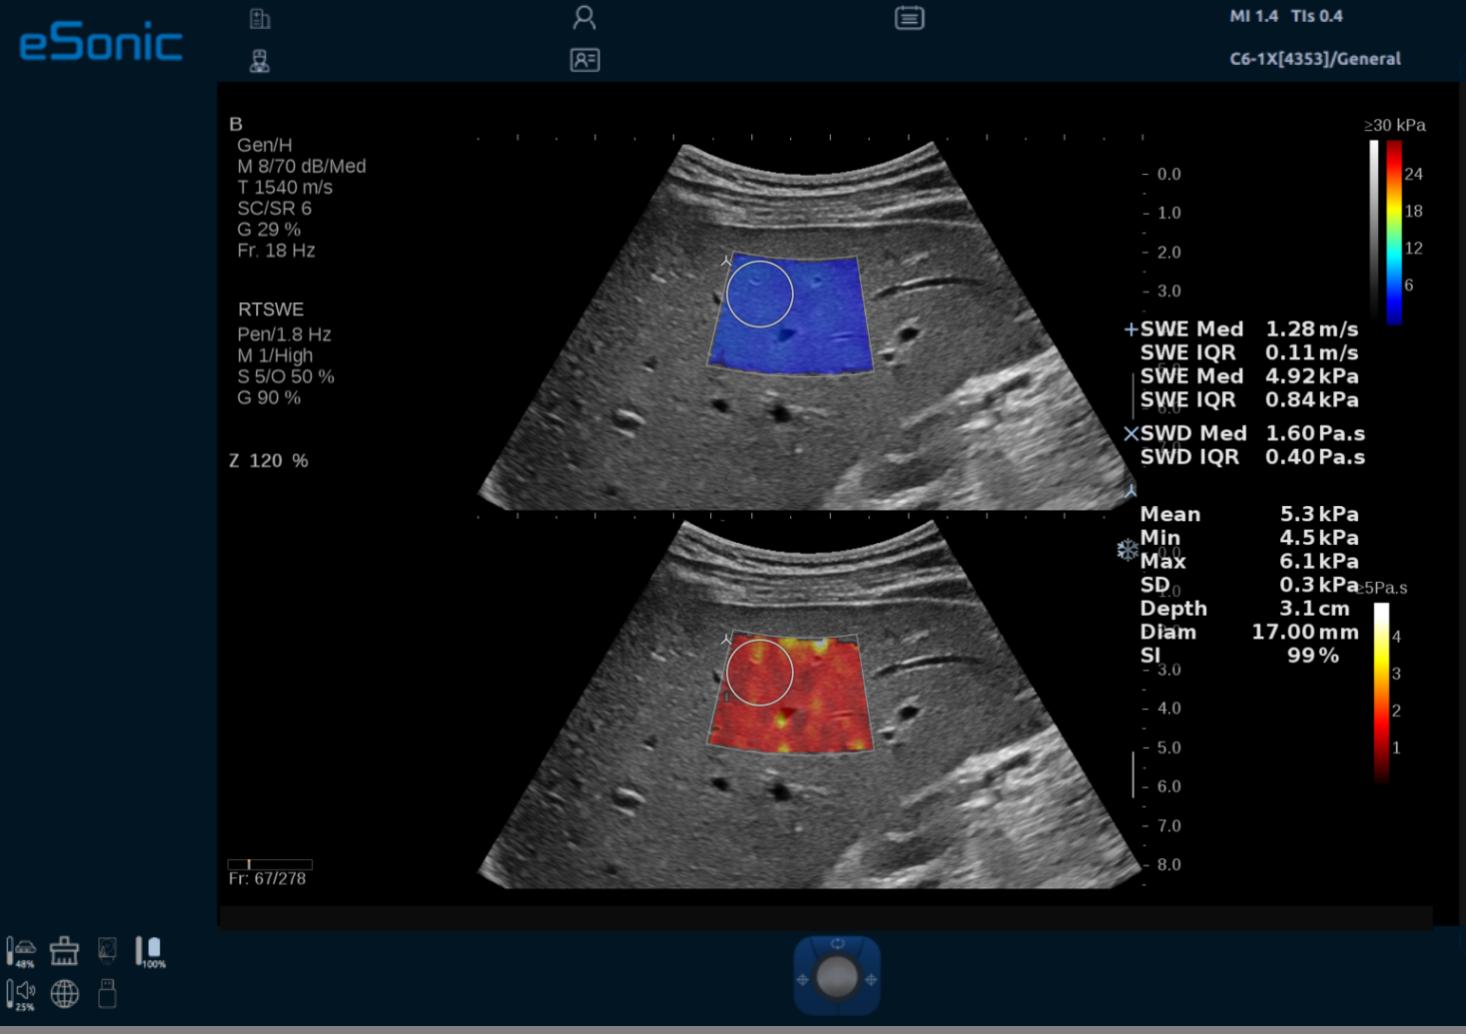

QVisco 粘弹性定量成像